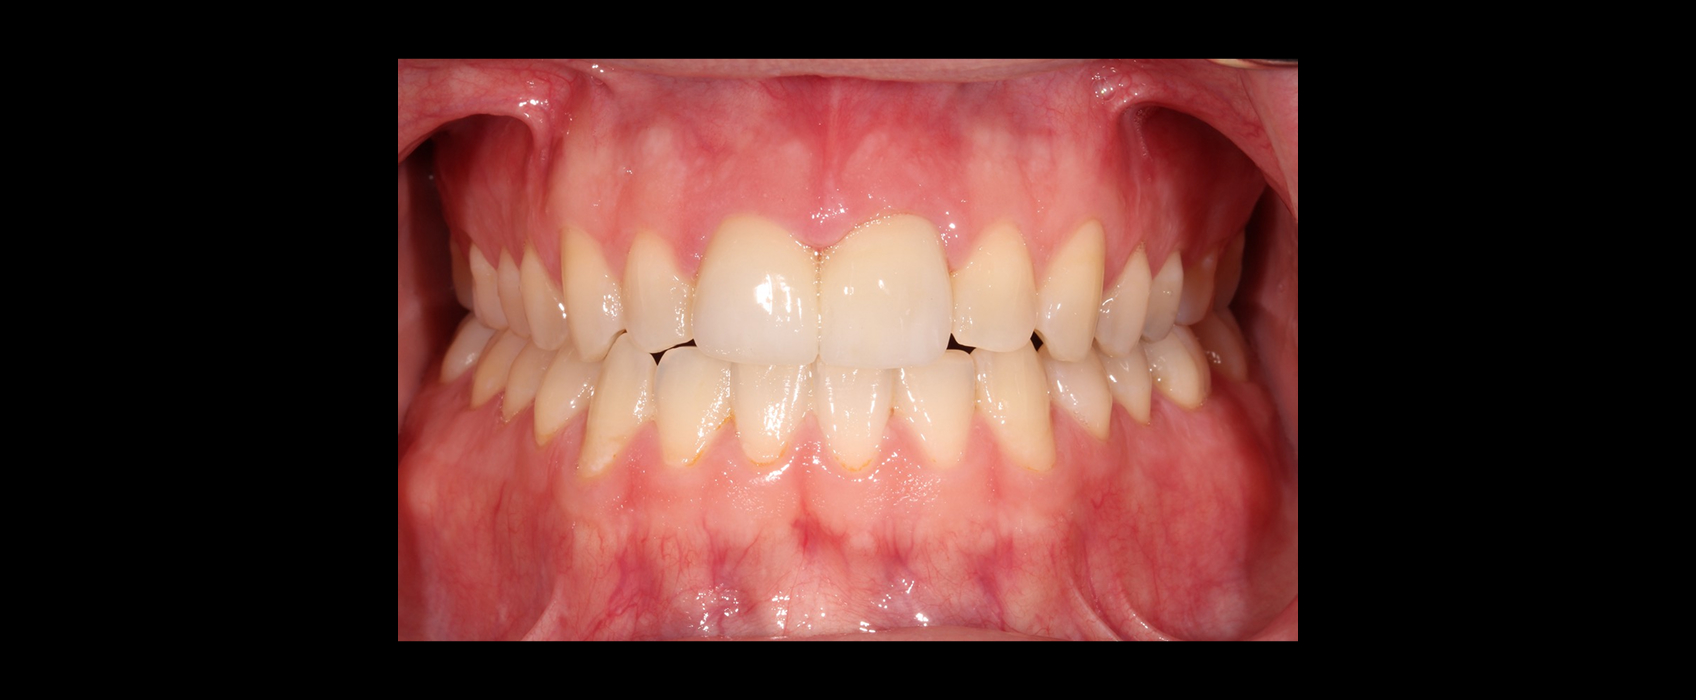

Clear aligners with attachments and elastics were used to correct the crossbite and improve tooth position. After 18 months, Zach’s teeth were in an ideal position for restorative care.

Restorative execution after orthodontic positioning

With the attachments removed, we prepared #8 and #9 and placed a diagnostic provisional to test esthetics and function. After one month with no occlusal adjustments needed, we moved forward with the definitive porcelain restorations.